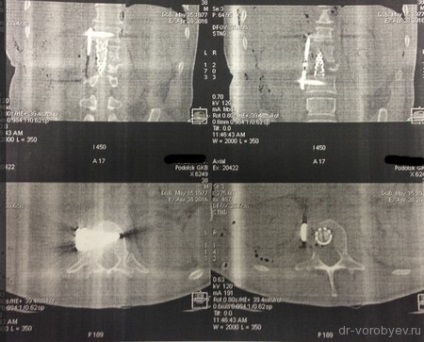

După un curs de detoxifiere și terapia masivă cu antibiotice pacientul a fost pregătit pentru o intervenție chirurgicală. Sa decis să efectueze îndepărtarea corpurilor vertebrale L1 L2 și discul între ele, iar placa corporodesis Masham umplut de os proprii (în acest caz, o margine) în China. Cel mai adesea, atunci când aveți nevoie pentru a manipula 1 vertebre vom trata accesul antero lateral deasupra sau dedesubtul diafragmei. În această situație, operarea cu cotorul de tranziție care implica doua fuziune vertebre apare între TN12 și L3, în total 4 trebuie să expună o vertebră și, prin urmare, a trebuit să folosească TORAKOFRENOLYUMBOTOMIYU. Accesul de-a lungul marginii cu deschiderea cavității pleurale și disectia retroperitoneale și diafragmei pe dreptul său semiperimetrul.

stadiu vizibil de funcționare după instalarea plasei între corpurile vertebrale. Operarea peste toracostomie placa spondylosyndesis (care a fost distrusă după ce a suferit purulent pleurita).

La filmele de control după implanturi chirurgie bună stare, decompresie este realizată în mod adecvat.